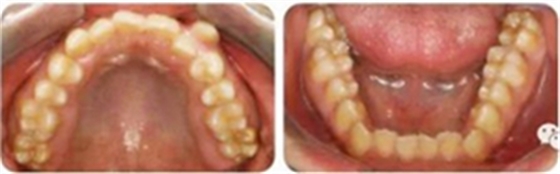

影像學(xué)檢查

無缺牙及多生牙,雙側(cè)下頜升支高度相等,智齒未萌。

頭影測量顯示為骨性Ⅲ類高角患者。